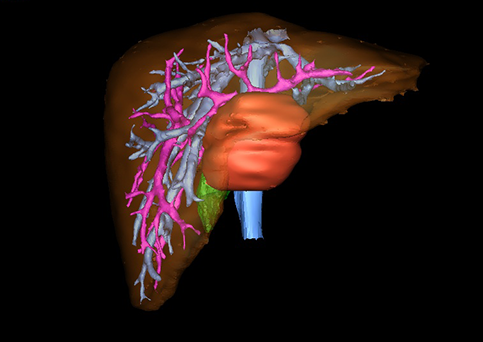

目前常用的检查方法有B超检查、CT、MRI、血管造影等。与其它的腹部肿块的诊断不同,对于小儿肝母细胞瘤血管造影具有重要的意义,可以作为手术前介入治疗的手段,也可为手术提供非常有效的影像学指导,但技术要求高,操作较复杂,且给患儿带来一定的痛苦。近年借助计算机辅助手术系统进行CT原始影像三维重建、手术规划和计算机虚拟手术技术,为精准肝脏手术提供了极为有效的技术支持。

近年来由于数字医学的发展,基于可视化三维重建技术的计算机辅助手术系统极大推进了小儿肝脏肿瘤的精准手术的进步。可以立体透视肝脏解剖、精确掌握肝段的边界、精确测算肝段乃至任意血管所支配的功能体积、准确定位病灶及其与邻近血管的解剖关系,最终对不同手术方案进行比较、筛选和优化。因此,计算机辅助手术规划系统是实现精准肝切除的有力辅助工具,是未来数字外科、精准外科等21世纪外科新理念的重要技术支撑。

计算机辅助手术规划系统具有良好的操作可行性、计算准确性和三维显示效果,可半透明、交互式显示真实的肝内立体解剖关系和空间管道变异,准确计算肝内管道的直径、走行角度,两点间的垂直距离,和任意血管的支配或引流范围等传统二维影像无法获取的信息,有助于实施个体化手术,提高了手术的确定性、预见性和可控性。计算机辅助手术规划系统可直观显示预留肝脏的结构和功能,并可通过虚拟切割功能辅助术者对手术方案进行蹄选和优化,系统评估手术风险和制定对策,改变了部分二维规划的术式和切除范围,使部分二维规划认为不能切除的患者成功手术,提高了手术的根治性、安全性和病变的可切除性,更加符合精准肝脏外科的术前规划要求。详见第11章。

随着计算机技术及影像检查技术的不断发展,以精确的术前影像学和功能评估、精细的手术操作为核心的精准肝切除技术日益受到重视。基于数字医学的计算机辅助手术技术(computer-assisted surgery,CAS)则是实现肝脏精准手术操作的基础。计算机辅助手术系统(CAS)可将术前二维(two dimensional,2D)的CT/MRI影像数据进行三维(three dimensional,3D)重建,建立个体化的肝脏三维解剖模型,清晰显示肝脏内脉管系统的走行及解剖关系,还原病灶与其周围脉管结构的立体解剖构象,准确地对病变进行定位、定性和评估,制定合理、定量的手术方案,实施个体化的肝脏血管取舍分配方案及实施精准肝脏手术。一般认为CAS包括:创建虚拟的患者的图像;患者图像的分析与深度处理;诊断、手术前规划、手术步骤的模拟;术中实时导航。应用本技术后,由于可以更清晰地看出肿瘤的界限,特别是根据肝血管的显影,判断出肿瘤与门静脉及肝静脉的关系以在手术前较准确地估计出手术成功切除的可行性。以往部分根据普通强化CT判断无法手术的病例而被评估为可以成功切除并手术成功。